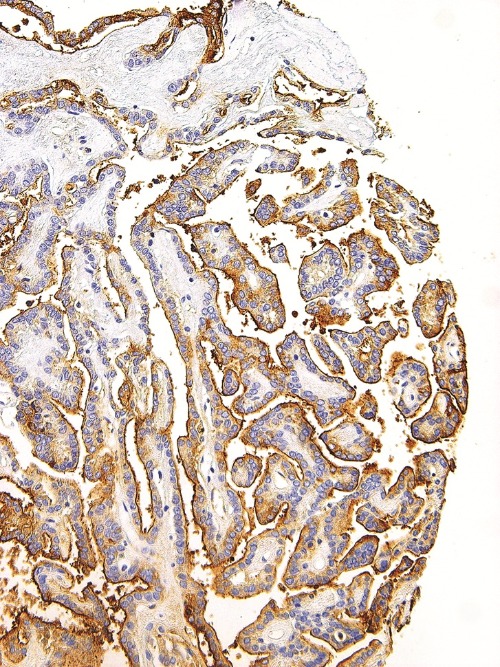

Immunohistochemical staining of human thyroid cancer tissue using Thyroglobulin Mouse Monoclonal Antibody (ARM577).

Thyroglobulin is a precursor to the thyroid hormones T4 and T3, and is present in the thyroid follicular cells. Nearly all thyroid follicular carcinomas stain for thyroglobulin and sometimes produce a focal staining pattern. Conversely, poorly differentiated carcinomas and non-thyroid adenocarcinomas do not stain for thyroglobulin, therefore Anti-Thyroglobulin is a useful diagnostic tool for recognizing papillary and follicular thyroid carcinomas. A panel of Anti-Thyroglobulin and Anti-Calcitonin is useful for identifying medullary thyroid carcinomas, whereas a panel of Anti-Thyroglobulin and Anti-TTF1 is useful for distinguishing between primary thyroid and lung neoplasms.